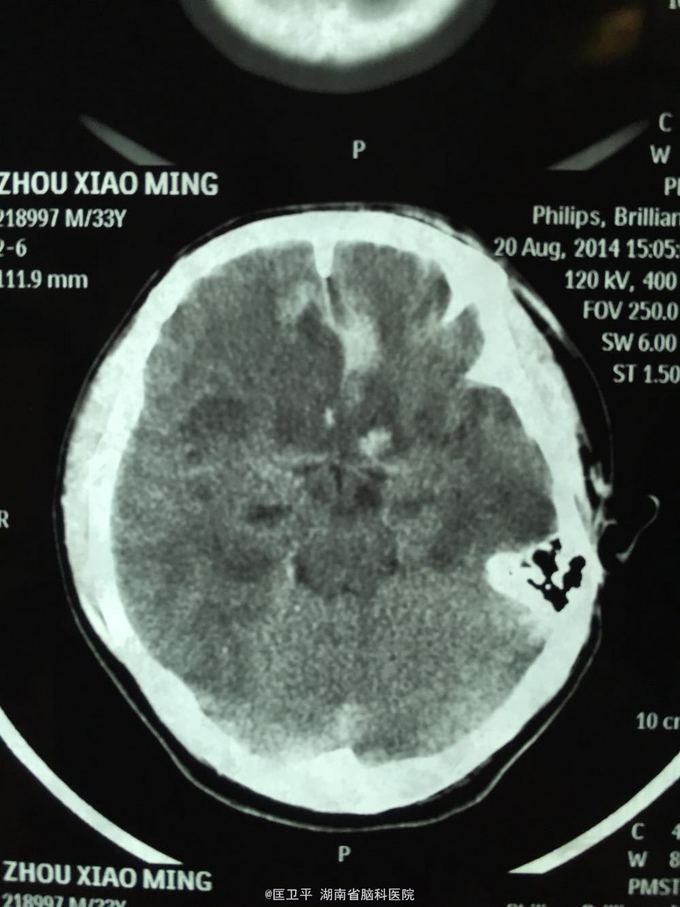

电击伤后智力低下,伤人毁物1年。 一年前在工地被电击伤昏迷,心跳呼吸停止,十几分钟后才有不规范的人工呼吸,持续约40分钟,心跳呼吸恢复。但患者智力低下,远近记忆很差,疑人害,伤人毁物严重,无法管理。

智力记忆恢复差,精神症状改善较好。